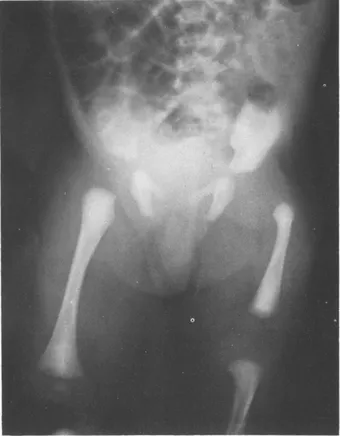

These vary with the degree of malformation. Those destined to develop simple femoral shortening alone will show no abnormality, whereas those in whom the hip joint and the greater part of the femur are absent will seem to have no femur and lack stability between the lower leg and pelvis. Most, however, display marked femoral shortening with flexion, abduction and external rotation deformity at the hip which is however stable and mobile from the position of fixed deformity ā Figure 1.1 ā findings which may cause surprise when the radiograph is seen. These features are important for they indicate that continuity exists between femur and pelvis in spite of radiological translucency in the area normally occupied by the proximal femoral shaft (Figure 1.2).

Figure 1.1 The Leg is short, flexed, abducted and externally rotated

Figure 1.2 The proximal femur is translucent but the acetabulum is well formed. The femur has not moved proximally and its tip is bulbous being situated at a greater distance from the acetabulum than on the normal side